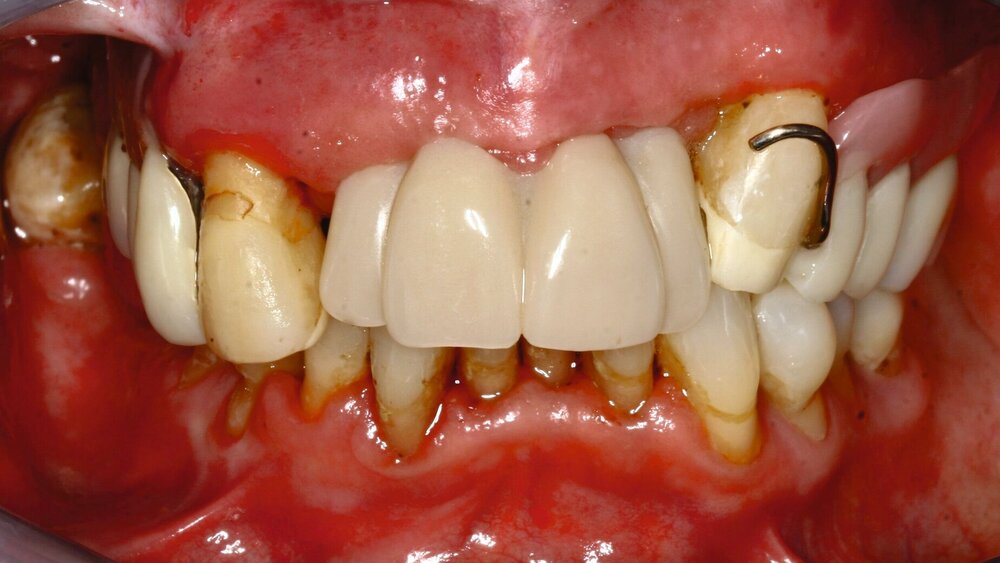

„Pflegebedürftige und Menschen mit Behinderungen können oft nicht mehr eigenverantwortlich für ihre Mundhygiene sorgen, die im Schnitt schlechter als die der übrigen Bevölkerung ist", betont Martin Hendges, Vorsitzender des Vorstandes der KZBV.

"Das Risiko für Karies-, Parodontal- und Mundschleimhauterkrankungen ist bei diesen Patienten besonders hoch. Daher ist es umso wichtiger, sie regelmäßig und zielgruppenspezifisch zahnmedizinisch zu versorgen. Speziell für ihre Bedarfe haben wir zugeschnittene Versorgungskonzepte entwickelt; das Leistungsspektrum wurde in den vergangenen Jahren erheblich erweitert. Die jetzt vorliegenden Daten zeigen den Erfolg und die Notwendigkeit dieses wichtigen Versorgungsangebots.“